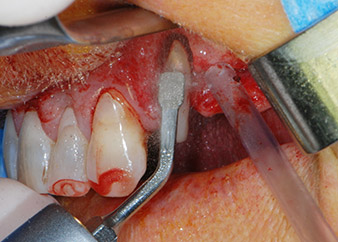

Zunächst wurde in einem Versuch, das Paro-Endo-Problem zu lösen, an der verbleibenden Wurzeloberfläche ein vorsichtiges Debridement mit einem piezochirurgischen Gerät vorgenommen (Piezomed, W&H) (Abb. 4); dann wurde der Apex mit dem gleichen Instrument im Sinne einer WSR abgetragen, um das verbleibende infizierte apikale Gewebe zu entfernen (Abb. 5). Eine retrograde Füllung war nicht notwendig, da die orthograde Füllung gerade revidiert worden war.